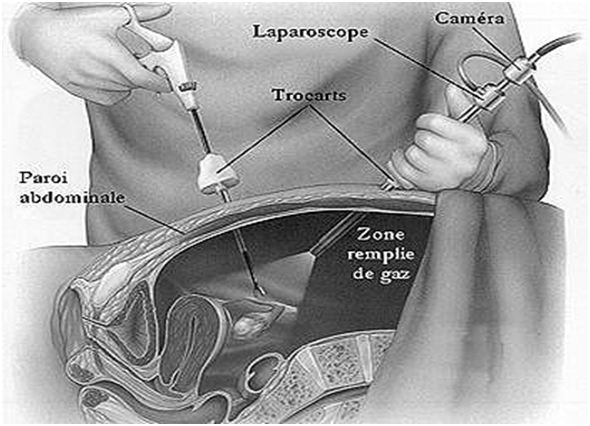

Заблуждения и факты о внутрибрюшной беременности